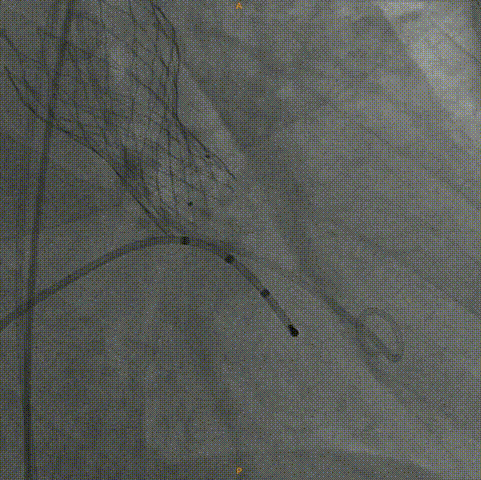

Venus26号瓣膜定位:结合瓣上结构考虑,采用0位释放。

Venus26号瓣膜释放:前三分之一慢放精准定位,中三分之一快放使瓣膜快速进入工作状态。

Venus26号瓣膜释放:位置良好,轻度反流,遂完全释放后采取后扩。

后扩后瓣膜最终形态。